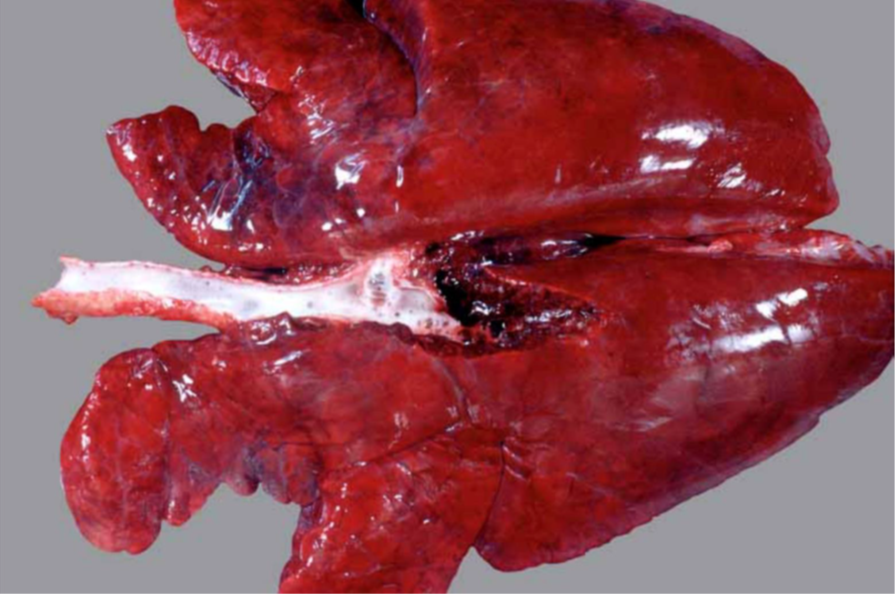

Schwein, Lunge: hochgradige, akute bis subakute, multifokale, fibrinöse Pleuropneumonie

- zufällige Verteilung der der Parenchym- und Pleuraveränderungen:

- in Spitzen- und Hauptlappen finden sich multiple landkartenähnliche Herde von roter bis dunkelroter Farbe und verfestigter Konsistenz

- multifokale, gelblichgraue Beläge auf der Pleura (= Fibrin), welche überwiegend mit den Herden des Parenchyms assoziiert sind

- Interstitien teilweise verbreitert

Ätiologie

- meistens, jedoch nicht ausschließlich, bakterielle Sekundär-Erreger nach primärer Virusinfektion

Erreger-Spektrum:

- vor allem gramnegative Bakterien (HAP-Gruppe), die Erreger besitzen Endotoxin (Lipopolysaccharid) und

bilden außerdem vielfach hochpotente Exotoxine (z.B. Apx-Toxine von Actinobacillus pleuropneumoniae)

H aemophilus (Glässerella) sp.

A ctinobacillus sp. (A. pleuropneumoniae = primäre Infektion beim Sw., außerdem A. suis und A. equuli)

P asteurella sp. (Mannheimia haemolytica (Rd.), P. multocida)

- außerdem aus der Familie der Pasteurellaceae: Histophilus somni (Rd.) und Bibersteinia trehalosi (Wdk.)

- Mycoplasmen (M. mycoides subsp. mycoides Small Colony Type, der Erreger der (anzeigepflichtigen!)

Lungenseuche des Rindes) und Mycoplasma bovis

- Pilze (Schimmelpilze)

Hintergrundwissen/ Infektionsweg/ Pathogenese

- die fibrinöse Pneumonie ist eine Form der Bronchopneumonie:

- aerogene Infektion > Bronchiolitis > peribronchioläre und endobronchioläre Fortleitung:

a) peribronchiolär > entlang der interstitiellen Lymphgefäße > Thrombose der Lymphgefäße > kein

Lymphabfluß (Gewebe ertrinkt und „stirbt“ im Ödem) > auf diesem Weg wird auch die Pleura erreicht

(Pleuropneumonie)

b) endobronchiolär > Alveolen füllen sich mit Entzündungsprodukten und Zellen an (Ödem, Fibrin, PMN,

Mø)

- makroskopisch typisch ist die kranioventrale Konsolidierung des Parenchyms; eine Ausnahme stellt die porzine

Pleuropneumonie* (APP) dar, weil die kaudalen Lungenlappen oft am stärksten betroffen sind

* meistens geht die fibrinöse Pneumonie mit einer fibrinösen Pleuritis einher > fibrinöse Pleuropneumonie

- neben der fibrinösen Komponente können auch Hämorrhagien und Nekrose (Sw: helle, landkartenähnliche und

trockene Herde in der gesamten Lunge) vorkommen

- die typische bunte Marmorierung des Parenchyms des Rindes entspricht dem klassischen (protrahierten) Ablauf in

vier Stadien:

1) Anschoppung

2) rote Hepatisation (leberähnlich, hepar = Leber)

3) graue Hepatisation

4) Organisation (Karnifikation)

- Komplikationen der fibrinösen (Pleuro-)Pneumonie: Sequester (v.a. Mykoplasmeninfektionen), Pleuraadhäsionen,

Abszesse bzw. Pleuraempyeme